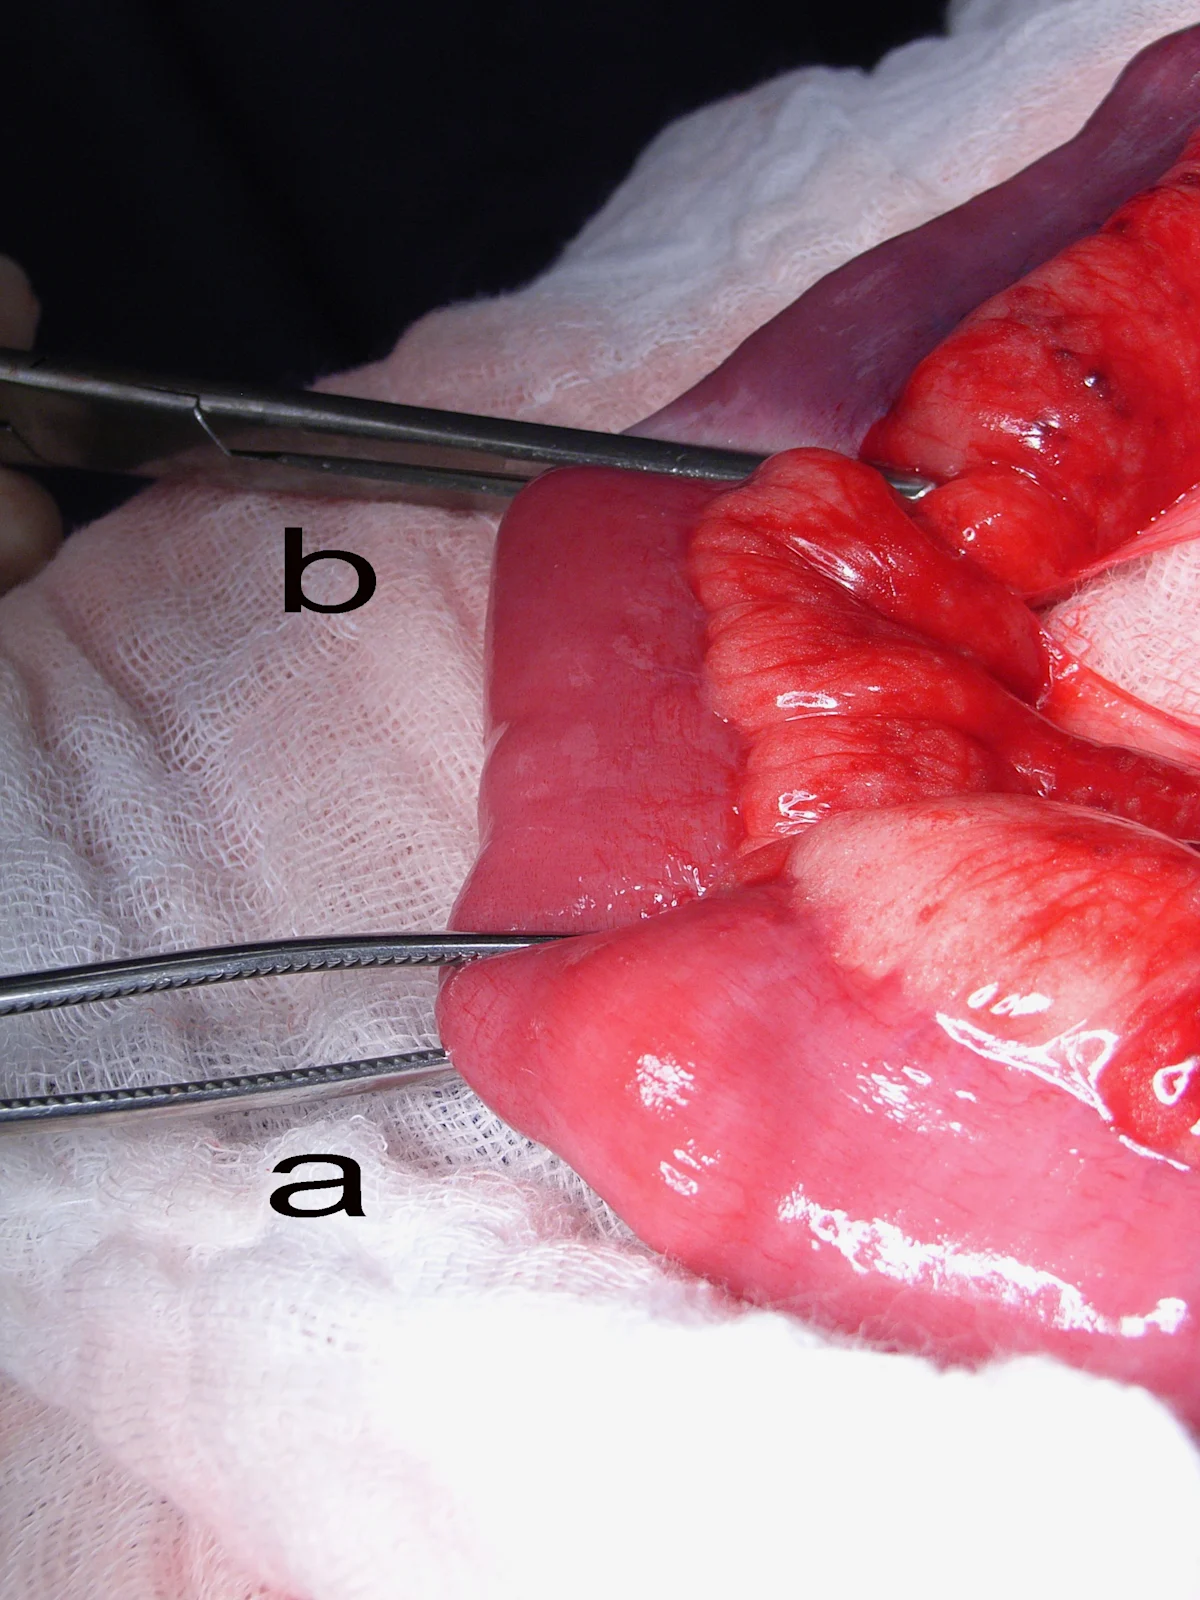

Crushing of the bowel ends can be minimized by grasping just the serosa of the bowel with the tips of the forceps. Note that the forceps on the left are handling the bowel by just grasping the serosa (correct), whereas the forceps on the right are grasping the full thickness of the bowel (incorrect).

Manually milk the contents from the bowel segment and occlude the lumen orad and aborad with noncrushing Doyen tissue forceps (a) or assistant’s fingers. This is done to prevent leakage of intestinal contents into the surgical site. Avoid crushing the bowel wall or mesenteric vasculature with this procedure. Place crushing forceps (b) just adjacent and inside the proposed transection, leaving at least 2 cm of healthy tissue between the 2 clamps.